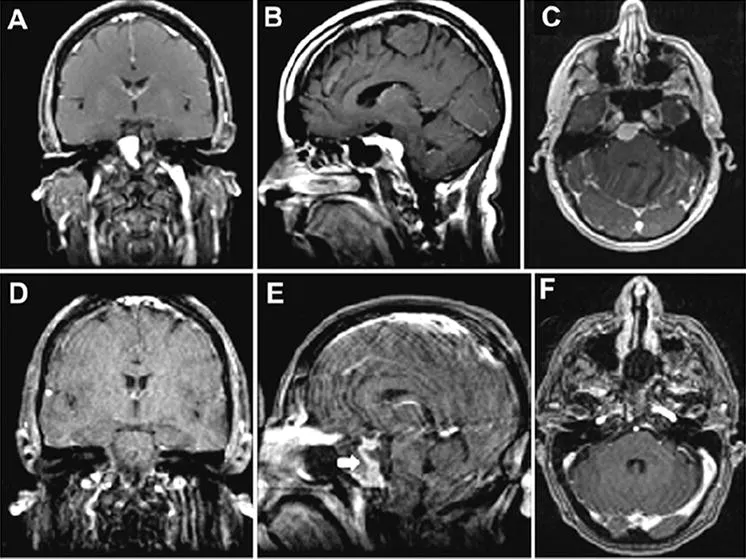

一位52岁女性患者表现为复视及间歇性头痛。体格检查发现,患者右眼外展功能受损。磁共振成像显示右侧岩斜交界处存在一均匀强化的肿块,伴有广泛的斜坡附着,提示为脑膜瘤(图6A-C)。手术团队实施了部分岩尖切除术。

术后磁共振证实肿瘤已完全切除(图6D-E),且未发现脑组织损伤。

注:手术中使用了带血管蒂的增强型鼻中隔皮瓣进行重建。患者在术后第7天出现了脑脊液漏。手术探查显示,漏液是由鼻中隔皮瓣的右上角移位所致,但该移位已得到成功且永久性的矫正。

患者术后恢复情况良好,复视症状消失,外展功能恢复正常。

图6:案例2。 一名岩斜区脑膜瘤患者通过EEA治疗的增强T1加权磁共振成像图像。术前冠状位(A)、矢状位(B)及轴位(C)图像显示起源于上斜坡的岩斜区脑膜瘤。肿瘤呈均匀强化,脑干受压,但未侵犯海绵窦。术后冠状位(D)、矢状位(E)及轴位(F)磁共振图像显示肿瘤已完全切除。E:图中的白色箭头指示带血供的增强重建鼻中隔皮瓣。